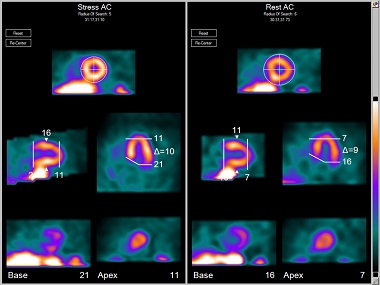

Emory Cardiac Toolbox

Provides advanced tools for cardiac SPECT and PET analysis, including comparison of perfusion to viability data, display of 3D images with coronary overlays and gated 3D cine, normal limits for agent match/mismatch as well as optional phase analysis for wall motion and evaluation of thickening.